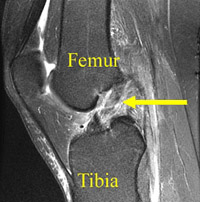

MRI of complete ACL tear. The ACL fibers have been disrupted and the ACL appears wavy in appearance [yellow arrow].